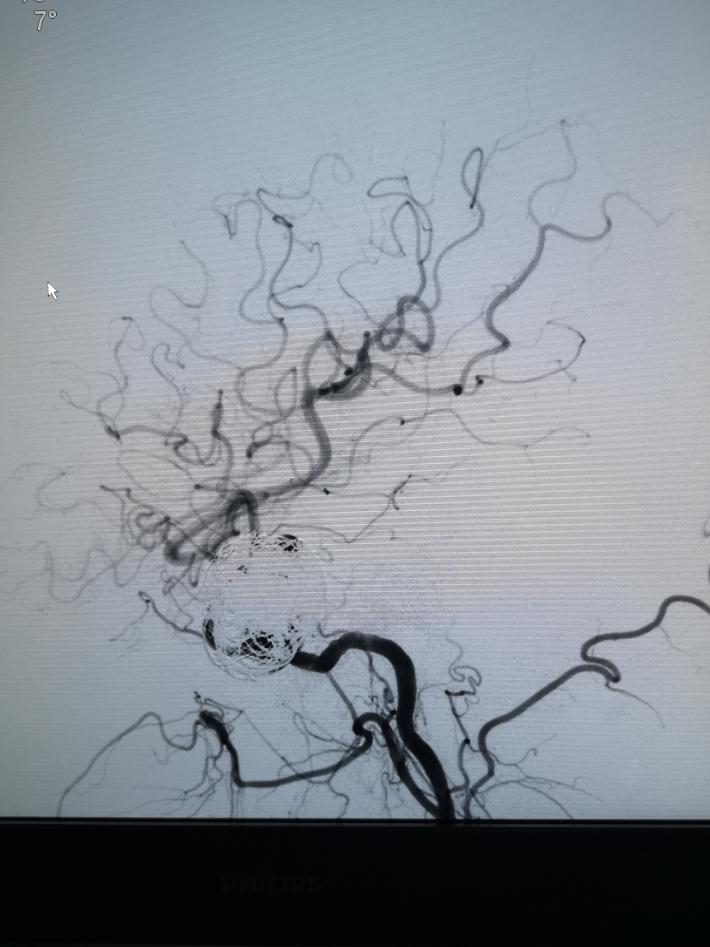

术中见海绵窦水平段巨大动脉瘤,瘤体造影剂明显滞留,且影响远端左侧远端血流。但前交通开放,对侧颈内动脉可完全代偿血流。

术后正侧位造影见,瘤体基本不显影,远端血流流速基本无延迟。